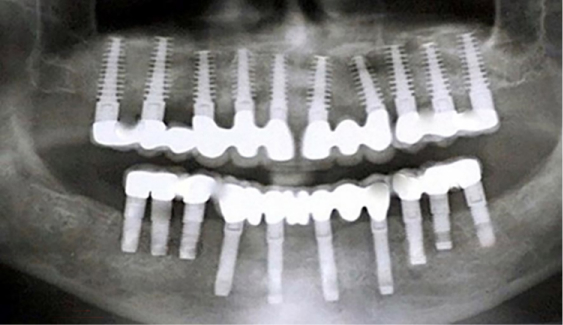

Implant Design and Positioning:

- Wider implants with poor-quality bone; longer implants whenever possible, with a min. of 8 mm length – 20mm.

- To obtain full-arch rehabilitation a min. of 6-8-10 implants are adequate, to achieve a predictable outcome.

- Computer-guided surgery minimizes errors in implant positioning.

- Implant position should be uniformly distributed along the alveolar arch and avoid distal cantilevers Implant Design

Different implant designs influence the biomechanics of the environment where an immediate implant is placed [15] International Journal of Oral & Maxillofacial Implants, 2022, v. 37, n. 2, p. 229, doi. 10.11607/jomi.2022.2.e. To enhance primary stability, self-tapping implants were developed, which compress the alveolar bone as the implant is inserted.

Achieving predictable Osseointegration: Primary stability.

- The splitting of implants reduces the stresses on the interfaces & enhances the stability, retention, and predictability of implants. The Splinting is attained by using a titanium bar of Ø1.0-1.5 mm, which is welded [19] labiolingually to all the placed implants, close to the gingiva utilizing the intraoral titanium welder [20], and is left in place for 3-4 months’ time. This splinting technique drastically reduces the risk of implant failure during chewing and helps in eliminating or minimizing the damage done by translation or lateral forces thereby evenly distributing the load and lessening the stress over immediately placed fixtures.